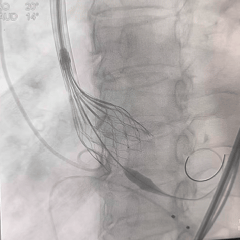

术中影像

TF29瓣膜,0位初始定位

全展开造影,大弯侧位置尚可

左侧位造影,小弯侧位置偏深

回收后调整瓣膜释放位置